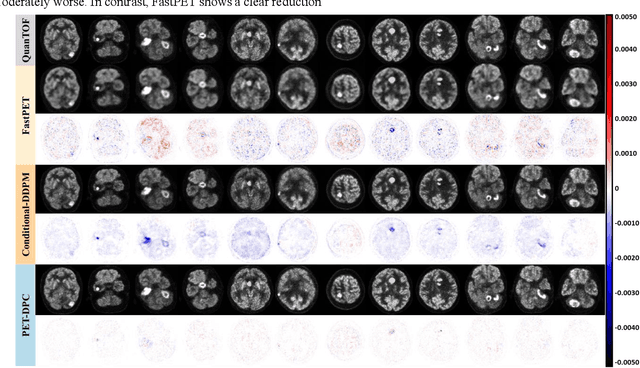

Abstract:Deep learning-based reconstruction of positron emission tomography(PET) data has gained increasing attention in recent years. While these methods achieve fast reconstruction,concerns remain regarding quantitative accuracy and the presence of artifacts,stemming from limited model interpretability,data driven dependence, and overfitting risks.These challenges have hindered clinical adoption.To address them,we propose a conditional diffusion model with posterior physical correction (PET-DPC) for PET image reconstruction. An innovative normalization procedure generates the input Geometric TOF Probabilistic Image (GTP-image),while physical information is incorporated during the diffusion sampling process to perform posterior scatter,attenuation,and random corrections. The model was trained and validated on 300 brain and 50 whole-body PET datasets,a physical phantom,and 20 simulated brain datasets. PET-DPC produced reconstructions closely aligned with fully corrected OSEM images,outperforming end-to-end deep learning models in quantitative metrics and,in some cases, surpassing traditional iterative methods. The model also generalized well to out-of-distribution(OOD) data. Compared to iterative methods,PET-DPC reduced reconstruction time by 50% for brain scans and 85% for whole-body scans. Ablation studies confirmed the critical role of posterior correction in implementing scatter and attenuation corrections,enhancing reconstruction accuracy. Experiments with physical phantoms further demonstrated PET-DPC's ability to preserve background uniformity and accurately reproduce tumor-to-background intensity ratios. Overall,these results highlight PET-DPC as a promising approach for rapid, quantitatively accurate PET reconstruction,with strong potential to improve clinical imaging workflows.